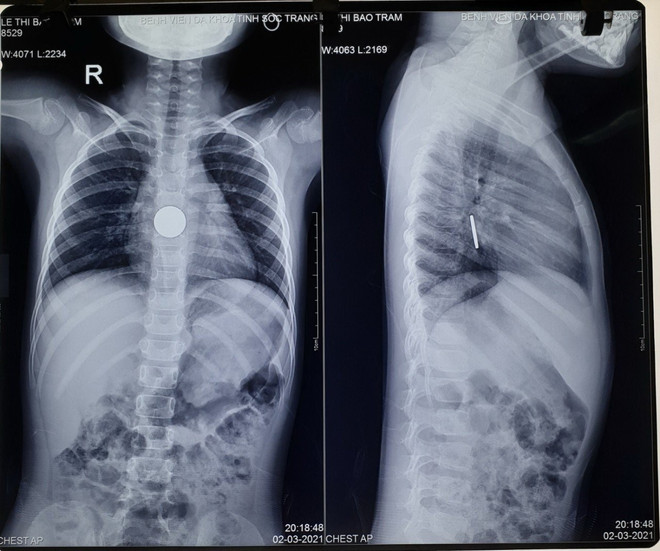

Sóc Trăng: Gắp thành công đồng xu trong bụng một bé gái ảnh 1Hình ảnh chụp X-quang cho thấy có dị vật trong ổ bụng. (Ảnh: Trung Hiếu/TTXVN)

Qua hình ảnh X-quang, dị vật trong bụng của một bé gái được xác định là đồng xu, đang kẹt ở vị trí cách cung hàm trên 25-26cm, rất gần với dạ dày.

Qua hình ảnh X-quang, dị vật được xác định là đồng xu, đang kẹt ở vị trí cách cung hàm trên 25-26cm, rất gần với dạ dày. Đây là một trường hợp rất khẩn cấp, nếu không kịp thời gắp dị vật, có thể dị vật sẽ gây ra tình trạng tắc ruột.